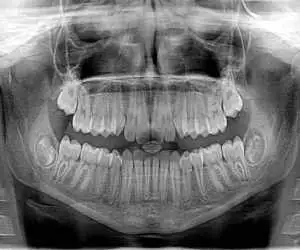

راهنمای جدید استفاده محتاطانه تر از رادیوگرافی در دندانپزشکی

به گزارش سرویس اقتصادی خبر ناب به نقل از همشهری - راهنمای جدید انجمن دندانپزشکی آمریکا (ADA} می گوید عکس برداری از دندان ها فقط در صورت ضرورت بالینی باید تجویز شود تا قرار گرفتن در معرض اشعه برای بیماران و افرادی که در مطب دندانپزشک کار می کنند به حداقل برسد.

این راهنمای جدید همچنین می گوید دندانپزشکان باید قبل از تجویز عکس برداری با اشعه ایکس، سلامت دهان و دندان فعلی فرد، سن او و هرگونه علائم و نشانه های پوسیدگی دندان یا سایر بیماری ها را در نظر بگیرند.